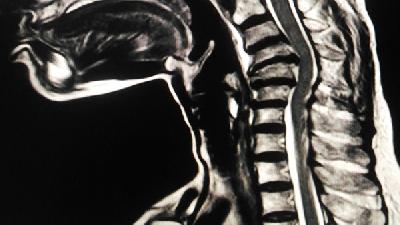

腰椎間盤突出的臨床表現(xiàn)比較復(fù)雜,人們很容易把腰椎間盤突出的臨床表現(xiàn)和其他疾病相混淆,那么,腰椎間盤突出的臨床表現(xiàn)有哪些呢?針對(duì)這個(gè)問(wèn)題,下面就來(lái)具體看看腰椎間盤突出的臨床表現(xiàn)。

(一)腰椎間盤突出的臨床表現(xiàn)之坐骨神經(jīng)痛

是腰椎間盤突出癥的主要癥狀,臨床上表現(xiàn)下肢坐骨神經(jīng)走行、支配區(qū)域疼痛。坐骨神經(jīng)痛的原因是神經(jīng)根或神經(jīng)干周圍存在慢性軟組織損傷,并與之發(fā)生粘連,腰椎間盤突出的臨床表現(xiàn)因受無(wú)菌性炎癥的刺激出現(xiàn)下肢刺痛,串痛或放射痛。我們將坐骨神經(jīng)痛分為根性和干性、根性疼痛一般受刺激位置在椎間孔周圍或椎管內(nèi),為椎管內(nèi)軟組織損傷,無(wú)菌性炎癥刺激所致。

(三)腰骶疼痛

腰突癥患者,絕大部分有腰骶疼痛,腰骶疼痛一般出現(xiàn)在腿痛之前,腰椎間盤突出的臨床表現(xiàn)為"先腰痛、后腿痛",雖然腰突癥主要以下肢痛為主,但是腰骰疼痛臨床中常見,發(fā)生腰骶疼痛的主要原因是椎管內(nèi)外損傷的軟組織,無(wú)菌性炎癥的化學(xué)性刺激作用于椎間外層纖維環(huán)及后縱韌帶中分布的竇椎神經(jīng)纖維,引起腰骶疼痛。